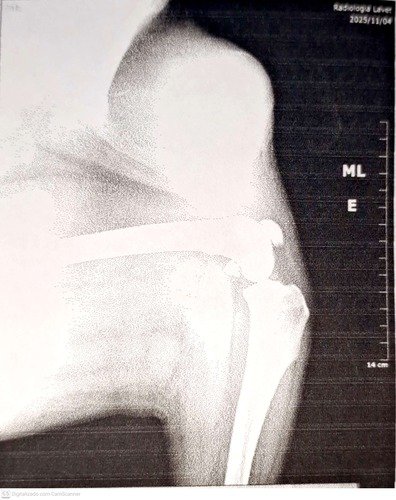

Hoje preciso passar por uma nova cirurgia para a retirada de um outro tumor, dessa vez na região da coxa esquerda. Começou com um pequeno nódulo que cresceu rapidamente, passei por um processo inflamatorio e foi até sugerido amputação total da perna. Mas meus tutores decidiram por não fazer a amputacao, devido a minha idade, fizemos um longo tratamento para conter a infecção e agora estou pronta para passar pelo procedimento cirurgico.